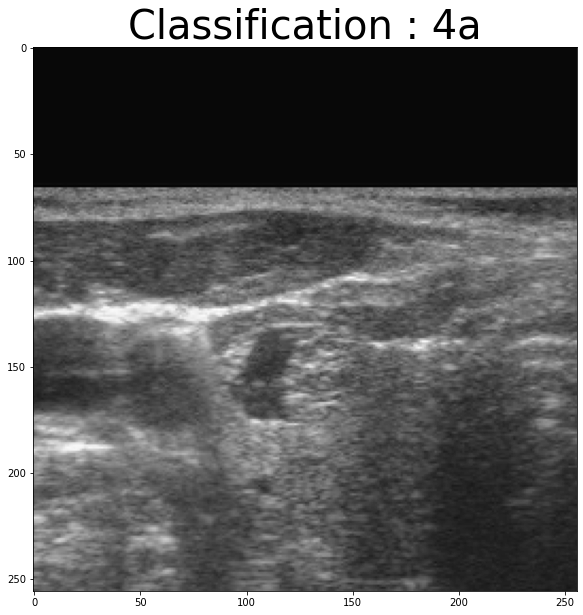

x=normalize(data)Let’s see , random examples from X :

import random

random_number=random. randint(0,len(df["Tirads"]))

plt.figure(figsize = (20,10))

tit="Classification : "+np.str(df["Tirads"][random_number])

plt.title(tit,fontsize = 40)

plt.imshow(x[random_number,:,:,0],cmap="gray")